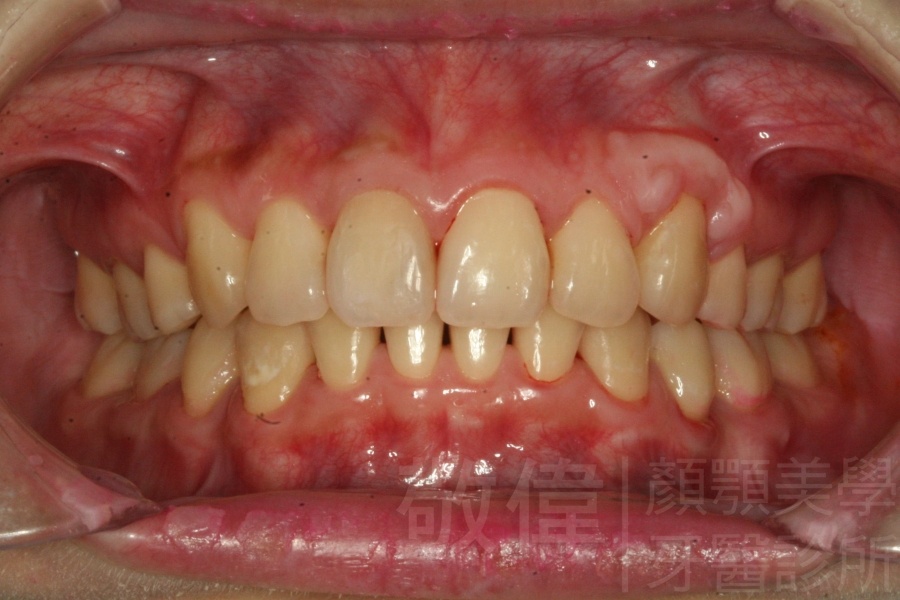

矯正後-右   矯正後-正   矯正後-左

上顎暴牙且牙齒極度混亂,經由矯正之後,臉型大幅度改善,牙齒的排列更加的整齊健康。相較於之前眼神充滿精神,自信心展現無遺。